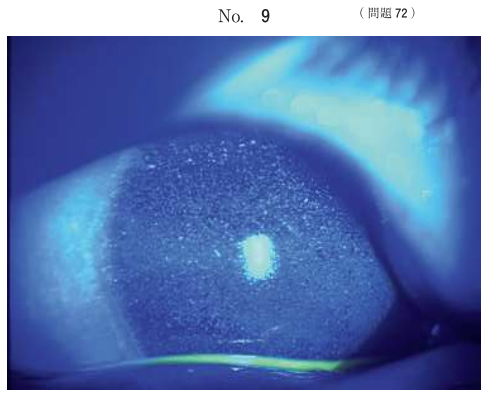

72 8 歳の男児。自閉症スペクトラム障害で偏食があり、白米、食パン及び白身魚しか食べようとしない。最近夜暗いところを手探りで行動し、目をよくこするため来院した。フルオレセイン染色後の左眼前眼部写真(別冊No. 9)を別に示す。右眼も同様の所見であった。 足りないと考えられる栄養素はどれか。

1.ビタミン A

2.ビタミン B

3.ビタミン C

4.ビタミン D

5.ビタミン E

正解・・1

白米、食パン、白身魚に含まれるビタミンはBやD。ビタミンAはレバー、ニンジン、海藻などに多く含まれます。

ビタミンAは、ロドプシン(杆体細胞に存在する光受容体タンパク質)の合成に必要な栄養素です。ビタミンA欠乏により、乾性角結膜炎がおこります。